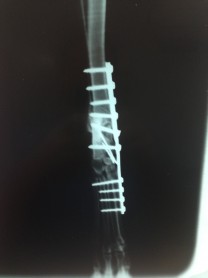

Casos Interessantes > ARTRODESE Tíbio-Tarsica por placa medial

Veja algumas Fotos